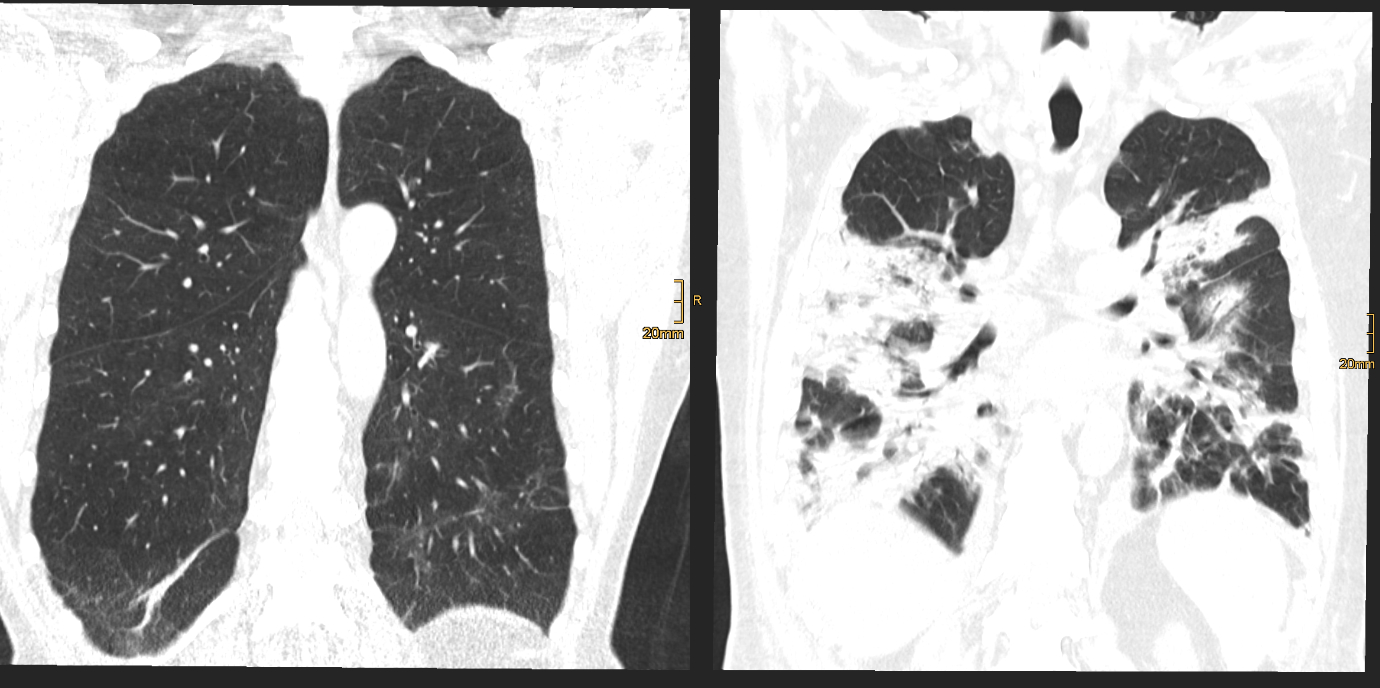

Eine aktuelle, kürzlich im angesehenen Fachjournal Radiology veröffentlichte Ein-Jahres-Folgestudie des Teams um den Radiologen Gerlig Widmann liefert nun neue Erkenntnisse zum Verlauf von Lungenveränderungen in der Computertomographie (CT) nach COVID-19. „In unserer viergeteilten Kohorte* betreffend den Schweregrad des initialen Verlaufes waren bei mehr als der Hälfte der Teilnehmer:innen auch noch zwölf Monate nach Krankenhausentlassung subtile Veränderungen im CT nachweisbar. Auch wenn eine Mehrheit dieses Anteils zumindest schwer erkrankt war, sind wir von diesem Ergebnis doch ein wenig überrascht. Der über 60-jährige männliche Patient mit kritischem Krankheitsverlauf trägt unseren Untersuchungen zufolge jedenfalls das größte Risiko, auch ein Jahr nach Covid-19 noch Lungenveränderungen im CT zu zeigen“, erklärt Radiologin und Erstautorin Anna Luger. Insgesamt wurden vier CT-Verlaufskontrollen der Lunge durchgeführt, von anfangs 142 Proband:innen konnten nach einem Jahr noch 91 Teilnehmer:innen in die Studie eingeschlossen werden.

Im Detail zeigten 34 Prozent der Teilnehmer:innen oberflächennahe netzartige Verdichtungen der Lunge, geringe Milchglastrübungen oder beides, bei 20 Prozent der Teilnehmer:innen waren ausgedehnte Milchglastrübungen, oberflächennahe netzartige Verdichtungen, Bronchialerweiterungen und mikrozystische Veränderungen feststellbar, die eventuell auf Vernarbungsprozesse hindeuten. „Aus radiologischer Sicht lässt sich noch nicht abschätzen, wie sich diese strukturellen Lungenveränderungen zeitlich weiter verhalten“, so der Leiter der Radiologie in der interdisziplinären Studiengruppe, Gerlig Widmann. Drei Szenarien seien jedoch vorstellbar: Die Veränderungen bilden sich langsam vollständig zurück, die Veränderungen halten an und es entwickeln sich stabile Vernarbungen, oder das Lungengewebe wird zunehmend fibrotisch (Bindegewebsvermehrung) und es kommt begleitend zu kontinuierlich zunehmenden klinischen Symptomen. „In jedem Fall“, so Widmann, „werden wir den Verlauf gemeinsam mit unseren klinischen Partnern weiter wissenschaftlich begleiten“.